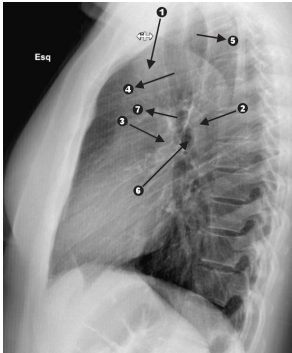

Observe a figura.

Identifique as estruturas assinaladas por números e setas.

A sequência correta, na ordem apresentada, é: